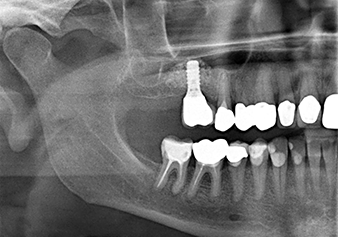

49-летняя пациентка, некурящая и не имеющая ничего примечательного в общей истории болезни, была направлена в нашу хирургическую стоматологическую клинику для хирургического удаления зуба 16 и последующей имплантации. После удаления зуба пациентка перенесла синусит в легкой форме, в результате чего мы сначала выждали шесть месяцев перед проведением операции. Остаточная высота кости при запланированном положении имплантата составляла 3-4 мм (рис. 1 и 2).

Рис.1: Предоперационные данные: Альвеолярный гребень хорошо зажил, включая достаточно широкую, кератинизированную десну.